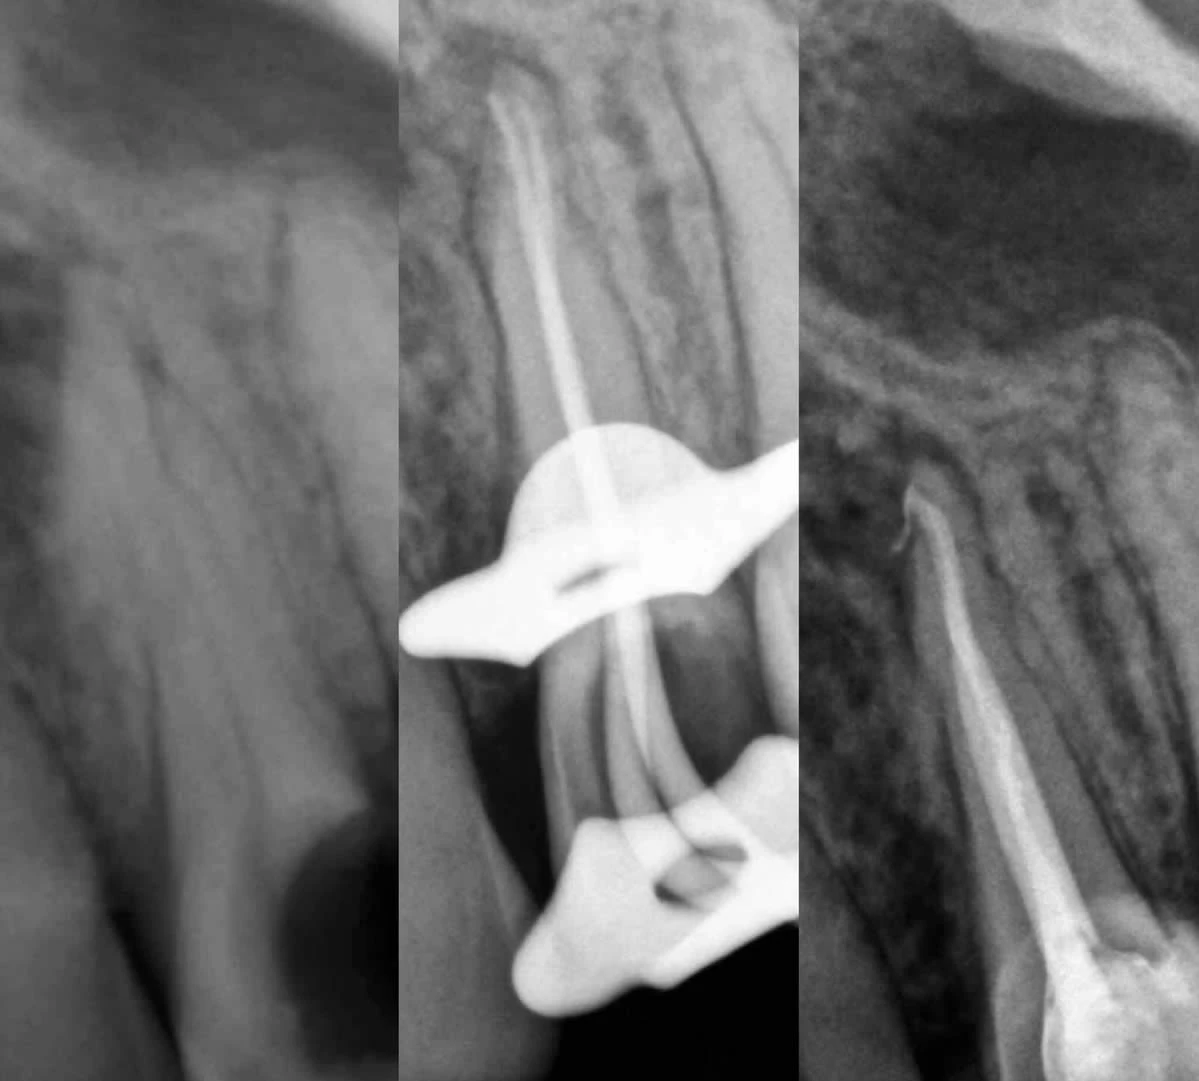

La devitalizzazione o cura canalare eseguita nello studio dentistico, consiste nella rimozione della polpa dentale e dei residui batterici presenti nel canale radicolare, nella disinfezione e allargamento dello stesso e conseguente riempimento con materiale inerte.

Si ricorre alla terapia endodontica quando il dente risulta danneggiato da processi cariosi molto profondi, traumi o altre cause, i batteri e le loro tossine penetrano nella polpa dentale determinando un’ infiammazione della polpa (nervo) che è molto dolorosa ( pulpite) . Se tale situazione, non viene trattata con la cura canalare, può formarsi un’infiammazione all’apice della radice del dente spesso associata a dolore e gonfiore (ascesso). Nei casi in cui il paziente non avverte alcun dolore, le tossine rilasciate dai germi possono creare dei processi infiammatori all’apice radicolare (granulomi, cisti), causando, nei casi clinici più gravi la perdita dell’elemento dentale.